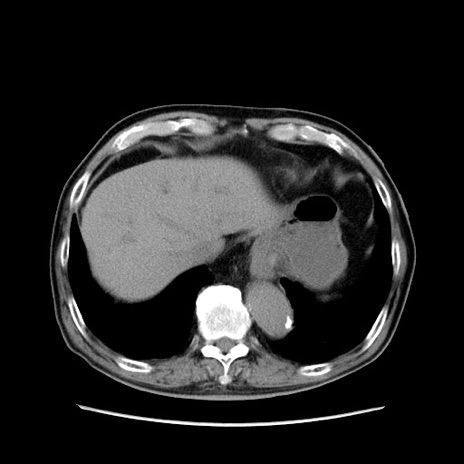

症例24(横断像)

【症例】80歳代男性

【主訴】左側腹部痛、嘔吐

【現病歴】本日早朝より左腹部に痛みあり。昼頃嘔吐認めたため、救急要請。

【既往歴】直腸癌(Mile手術)、胆摘

【身体所見】意識清明、BT 35.9℃、BP 221/93mmHg、SpO2 97%(RA) 、腹部:左ストーマ周囲に限局性の腹部膨隆あり。 膨隆部自発痛・圧痛あり・軟。

【データ】WBC 7700、CRP 0.09